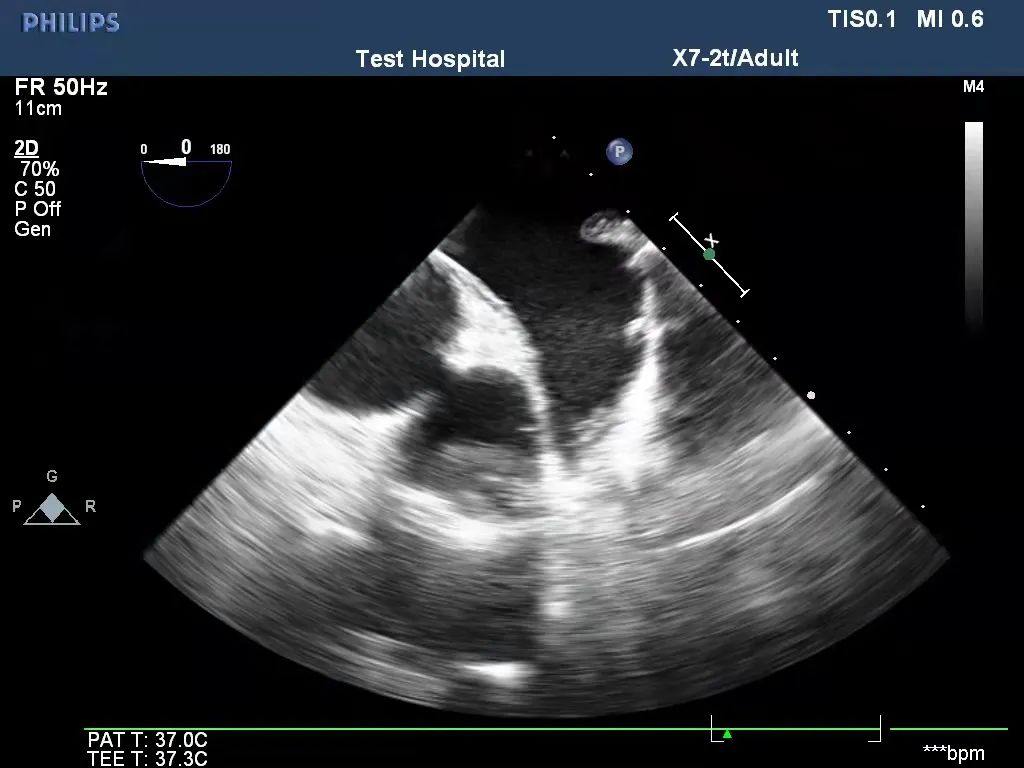

术前TEE评估左心耳

左心耳闭合后经TEE(经食道超声)和出院前的超声评估,左心耳根部未见明显残余(残余<1cm)、闭合夹无移位,左心耳与左心房间无血流(CDFI:未见血流交通)通过,完全符合左心耳外科闭合的国际专家共识,V-Clip®首例入组圆满成功。